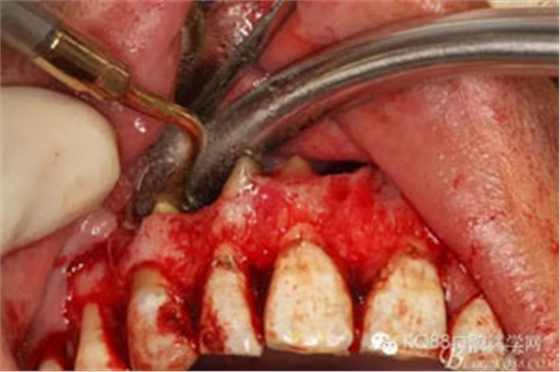

圖9.11/12/13的牙根完全裸露在囊腔內(nèi),13根尖牙膠尖超填過(guò)多。

圖10.超聲骨刀行11/12/13根尖切除術(shù)